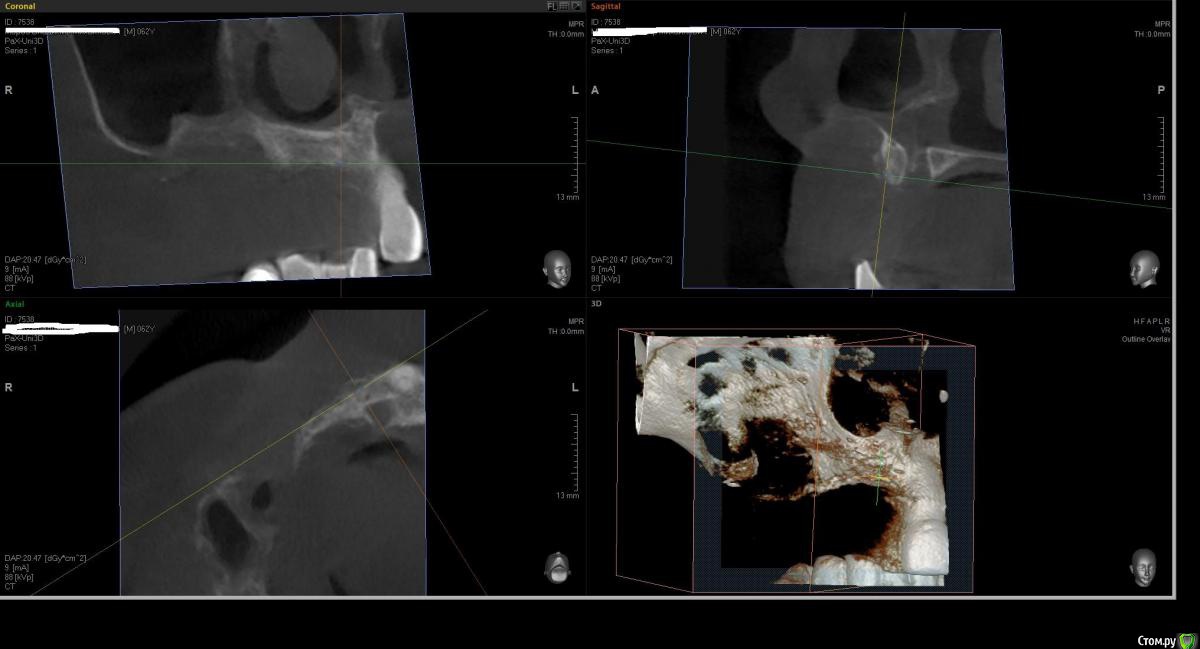

Kostoprav Опубликовано 1 августа, 2016 Поделиться Опубликовано 1 августа, 2016 что бы вы сделали в данной ситуации уважаемые коллеги? был синус и титановая сетка во фронте но увы все прокисло ((( 1 Ссылка на комментарий

Kostoprav Опубликовано 2 августа, 2016 Автор Поделиться Опубликовано 2 августа, 2016 Всё вычистить, подождать заживление и повторить.это кт уже после чистки, а повторить снова титановой сеткой?думаю снова сетка здесь не прокатит( Ссылка на комментарий

Kostoprav Опубликовано 3 августа, 2016 Автор Поделиться Опубликовано 3 августа, 2016 скисло через 3 мес, до этого все было идеально!но меня больше беспокоит вопрос что теперь с этим делать, там теперь кости особенно во фронте почти нет.какую технику использовать? Ссылка на комментарий

Fibez Опубликовано 3 августа, 2016 Поделиться Опубликовано 3 августа, 2016 Меня не удивляет что резорбировался графт под сеткой. Но где тут графт в пазухе? Что там было с синуслифтингом? Ссылка на комментарий

Kostoprav Опубликовано 3 августа, 2016 Автор Поделиться Опубликовано 3 августа, 2016 Меня не удивляет что резорбировался графт под сеткой. Но где тут графт в пазухе? Что там было с синуслифтингомначалось все как раз из синуса. пазуха разделена перегородкой, я поднял дно только в передней камере Ссылка на комментарий